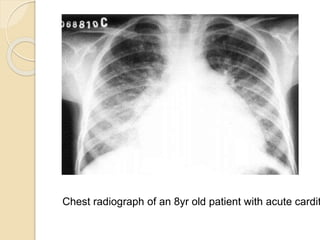

Chest radiograph of an 8yr old patient with acute cardit

Carditis – Pathology